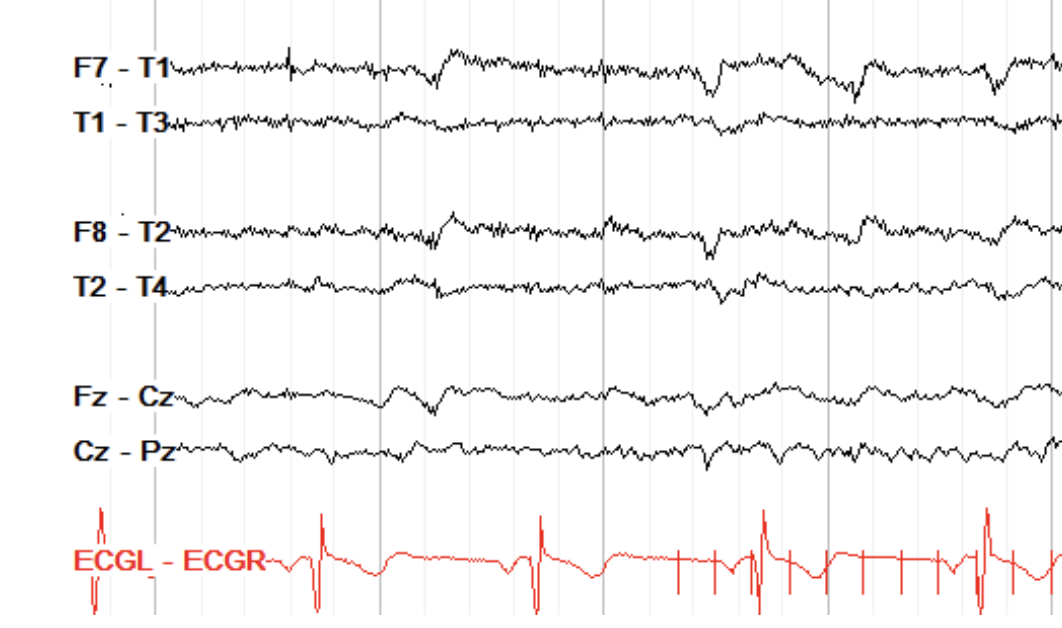

Time locked to QRS. MOSTLY ON LEFT.

ECG art